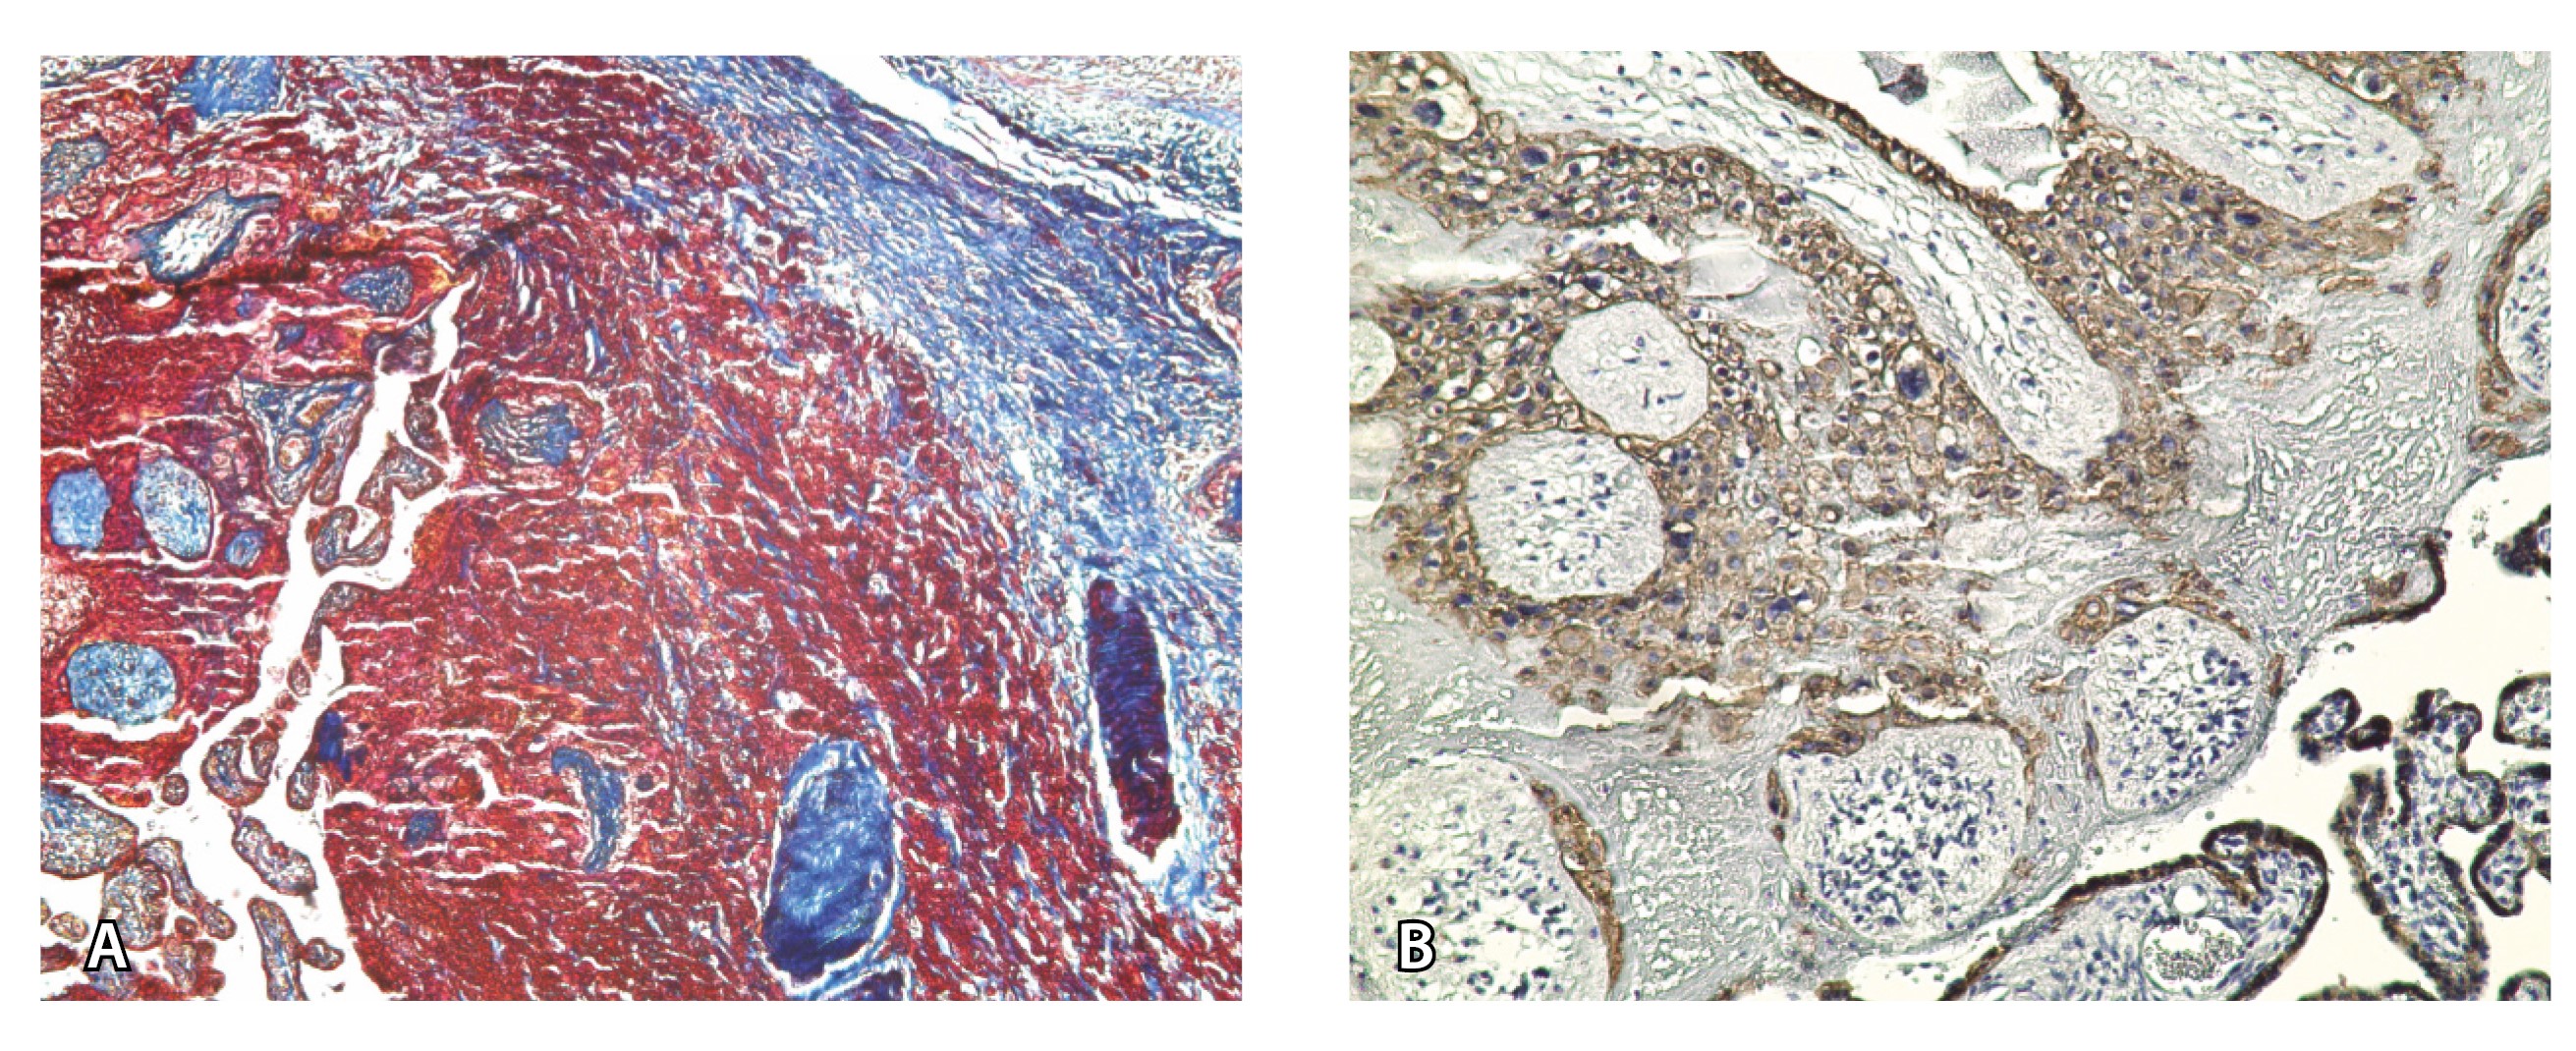

Главным отличием крупных сосудов в составе серозной оболочки является то, что морфологически они находятся в пределах стенки матки. Об этом свидетельствует наличие в операционном материале тонкого поверхностного слоя мезотелия, отделяющего матку от брюшной полости (рис. 11). Его невозможно визуализировать методом МРТ из-за особенностей метода и толщины получаемых срезов.

Рис. 11. Сосуды 4-го типа при гиперваскуляризации стенки матки при патологической инвазии: А – крупный сосуд в составе серозной оболочки матки: справа видны единичные цитотрофобластические клетки (стрелки), не достигающие стенки артерии (иммуногистохимическое исследование, маркер цитокератин 8; × 50); Б – крупные сосуды в составе серозной оболочки: наличие внутреннего слоя эндотелиоцитов (иммуногистохимическое исследование, маркер СD34; × 50)

На микропрепаратах васкуляризация серозной оболочки представлена множеством крупных сосудов, идущих в разных направлениях и анастомозирующих друг с другом. Возможно, имеются артериовенозные соустья. На серийных срезах также видно, что в стенках артерий трудно различимы два слоя миоцитов (продольный и поперечный). Со стороны адвентиции они окружены толстым «футляром» из грубоволокнистой голубой ткани (при окраске по Маллори). Она проникает в стенку артерий, замещая мышечный слой (рис. 12).

Рис. 12. Истончение миометрия; в составе серозной оболочки видна крупная артерия, окруженная плотной соединительной тканью. А – cосуды в составе серозной оболочки (окраска по Маллори; × 200), не дифференцированная на мышечные оболочки стенка артерии, справа – вена, оба сосуда покрыты фиброзной оболочкой, внизу виден слой мезотелия в составе серозной оболочки; Б – серийный срез тех же сосудов при окраске на выявление эластических волокон, сосуд с соединительнотканной муфтой (окраска по Вейгерту; × 50): определяется полная дезорганизация эластичного материала в стенке; стрелкой указан мезотелий (аналог pl. increta, PAS 2 по FIGO)

Эластический каркас представлен сетью тонких волокон, без концентрации на внутреннюю и внешнюю мембраны. Однако маркер СD34 констатирует сохранение эндотелия, что свидетельствует о том, что по артериям циркулирует кровь, не сворачиваясь (рис. 13).

Рис. 13. Самые крупные сосуды в пределах серозной оболочки стенки матки: А, Б – серийные срезы артерии; × 50. При окраске по Маллори (А) видна тонкая полоска мезотелия (черная стрелка), слабо дифференцированная мышечная стенка артерии, вокруг нее – плотная коллагеновая оболочка (желтая стрелка), в просвете определяются тромботические массы. При окраске по Вейгерту (Б) наблюдается полная потеря внутренней и внешней эластических мембран